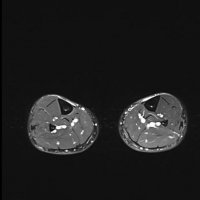

MRI is the most sensitive radiological examination (~88%). It may demonstrate a spectrum of findings ranging from normal to periosteal fluid to marrow edema to actual stress fracture. The medial cortex (+/- posterior cortex) is most commonly affected.